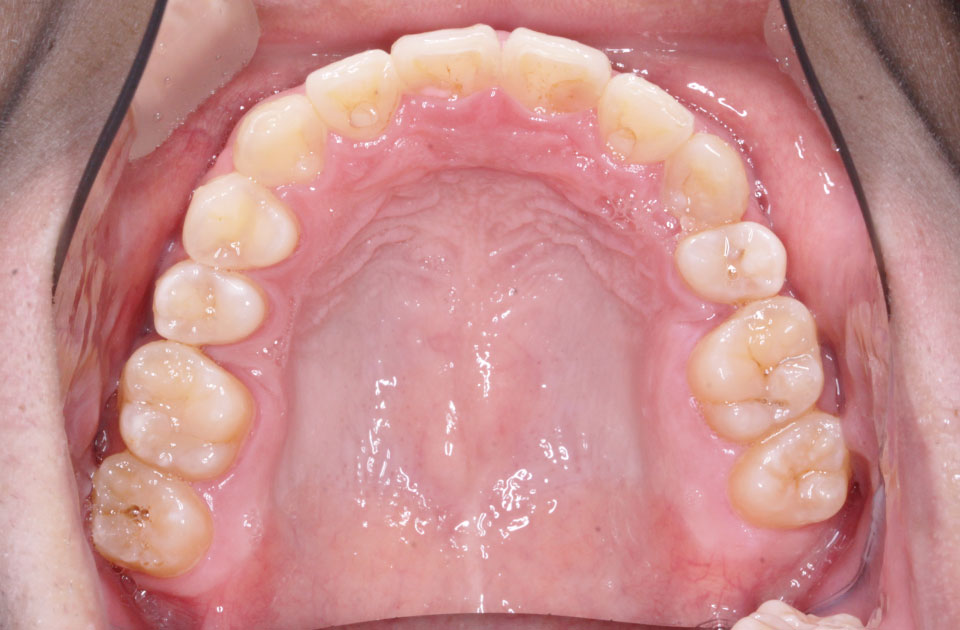

矯正前 上顎

矯正後 上顎